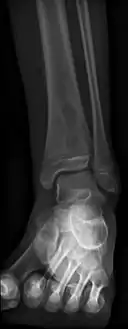

Usually occurs at the metaphysis of long bones. Distal tibia, proximal tibia, distal femur, proximal or distal fibula, and distal radius.

Oval, elliptical, or serpentine radiolucency usually greater than 1 cm surrounded by a heavily reactive sclerosis, granulation tissue, and a nidus often less than 1 cm. The margins often appear scalloped on radiograph. Brodie's abscess is best visualized using computed tomography (CT) scan. Associated atrophy of soft tissue near the site of infection and shortening of the affected bone. Osteoblastoma may be a classic sign for Brodie's abscess.